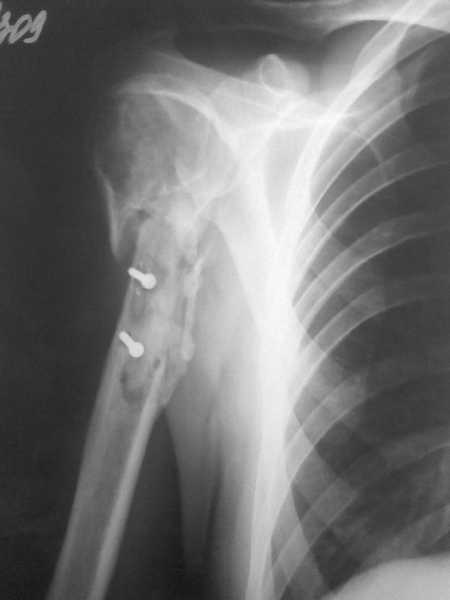

[Ortho] Ложный сустав в/3 плечевой кости!

Здравствуйте, коллеги!!! К нам в отделение госпитализирован пациент 39 лет с

клинико-рентгенологической картиной ложного сустава в/3 плечевой кости! Снимки

прилагаются! Предистория такова: около года назад получил оскольчатый перелом в/3

плечевой кости. В одной из московских больниц выполнен остеосинтез пластиной, через

несколько месяцев выполнен реостеосинтез, опять же пластной...., причины реостеосинтеза

со слов пациента таковы - "доктору не понравилась как лежит пластина и он ее переложил..." -

два месяца назад выполнено удаление фиксатора. Никаких выписок у больного нет. Около недели

обратился в травмопункт, откуда направлен к нам. Клинически у пациента имеется подвижность

в области в\3 плеча, костная крепитация, умеренная болезненность в в/3 плеча при движениях,

атрофия дельтовидной мышцы. На следующей недели планируем пациента опериравать. Коллеги,

у нас возникло несколько вопросов, если не затруднит, то посоветуйте и подскажите... Мы

планируем выполнить закрытый блокируемый остеосинтез, скажите пожалуйста, нужно ли в этом

случае, на ваш взгляд, выполнять костную пластику или достаточно выполнить рассверливание

костномозгового канала и заштифтовать толстым гвоздем, нужно ли пытаться удалить винты???